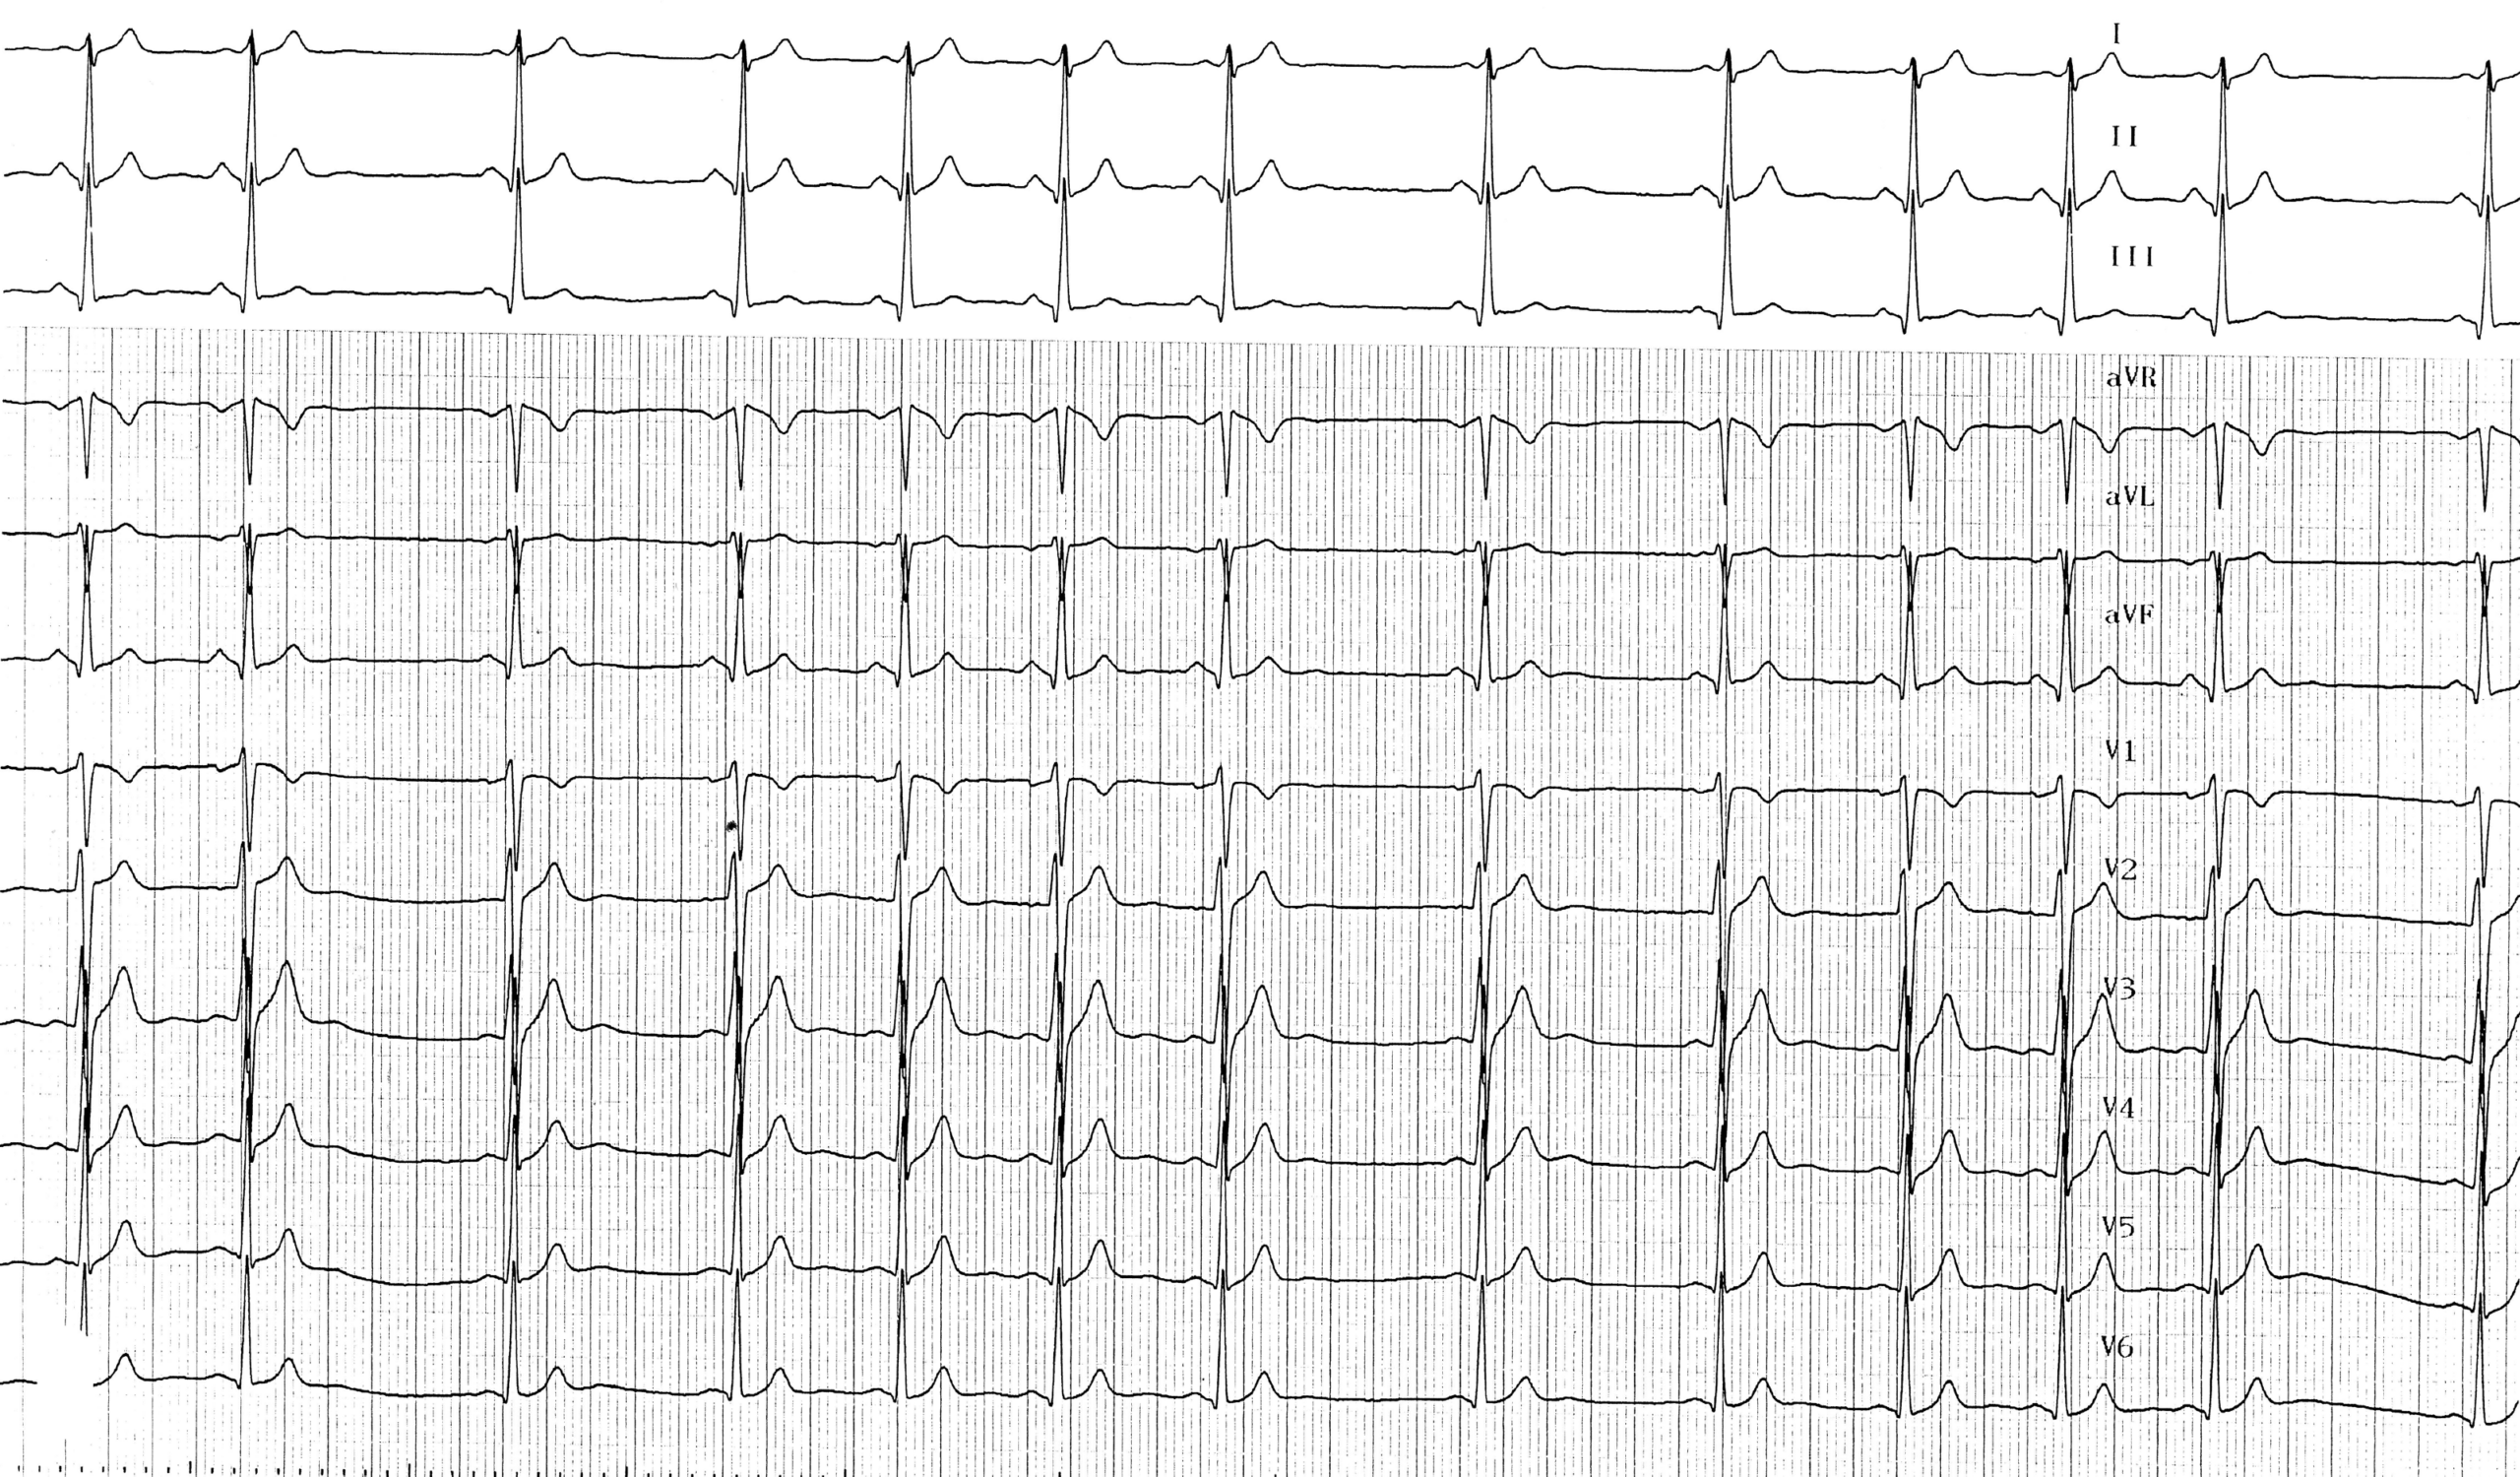

Sur l’électrocardiogramme, l’arythmie sinusale respiratoire phasique se traduit par un rythme à commande sinusale dont la fréquence est nettement irrégulière. On retrouve donc:

• Des ondes P identiques sans modification de morphologie;

• Une irrégularité des ondes P présentant des écarts de plus de 160 ms entre les intervalles PP;

• Les variations de durée des cycles PP sont périodiques et suivent les cycles respiratoires; une accélération du rythme sinusal est observée à la fin de l’expiration (reprise du tonus vagal) alors qu’un ralentissement du rythme sinusal survient à la fin de l’inspiration et au début de l’expiration (baisse du tonus vagal); ces variations disparaissent lors des apnées et diminuent lors d’un effort avec l’augmentation de la fréquence cardiaque;

• L’intervalle PR et le reste de l’électrocardiogramme sont généralement normaux;